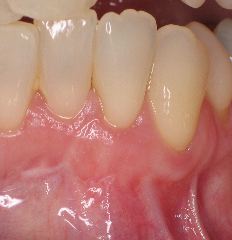

This is a the result at 2 months.